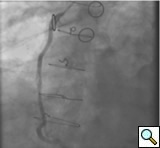

The most commonly used catheters for left heart catheterization and vein graft angiography can be seen in Figure 1 and Figure 4-13. Most of the vein grafts have horizontal take off and can be successfully engaged using a commonly used Judkins right number 4 (JR4) catheter. The JR4 catheter is the most commonly used catheter for the engagement of the right coronary ostium with horizontal take off. However, many vein grafts have unusual take off requiring different catheters. Many right coronary vein grafts have steep inferior take off making the ostial engagement with JR4 difficult or impossible (Figure 10). In such a scenario, a multipurpose catheter which has a shallow angulation is the best choice (Figure 11). The second major challenge in engaging vein graft ostia, particularly vein grafts supplying the left coronary arteries, is the shape of the aorta. A large aorta can make it very difficult for the JR4 catheter to reach the ostial vein grafts. In such a situation, Amplatz (AR) right and left (AL) catheters can be very helpful to reach the vein graft ostia. Amplatz catheters have a larger primary curve and have been used successfully in unusual superior take off of left coronary arteries or vein grafts and in large aorta. Amplatz catheters are available in different sizes (from smaller to larger curve: AR 1, AR2, AL2, AL2 and AL3). Occasionally, a very superior take off of a vein graft requires specially designed bypass graft catheters. Amplatz catheters are also extremely helpful in engaging native right coronary ostium with anterior take off.

PCI of the vein and arterial grafts have unique challenges. For any PCI, guide support is very important for successful balloon and stent delivery. In a tortuous vein graft with a steep angle, advancement of a stent can be very difficult and challenging. Therefore, it is important to choose the best available catheter before starting PCI. Similar to the right coronary angiography, a JR4 guide catheter is most commonly used in this setting. However, Amplatz guide catheters for left vein grafts and multipurpose catheters for right vein grafts are better choices in certain anatomy. In Figure 8 and Figure 10 two examples of poor guide support in two vein graft interventions can be seen. Initially, a JR4 guide was used for PCI of the vein graft supplying the left anterior descending artery (LAD) without any success. However, after changing the guide to an Amplatz left 2 guide catheter, we achieved excellent support without any difficulty in advancing two stents (Figure 9). In Figure 10, difficulty is illustrated in engaging the vein graft ostium supplying the right coronary artery with a JR4 catheter. This vein graft has a very steep inferior take off from the aorta. After changing the guide to a multipurpose catheter, we were able to deliver three stents successfully without any difficulties (Figure 11). Similar challenges exist in the treatment of the left IMA or right IMA. These arterial grafts can be extremely tortuous making stent delivery very difficult. It may be necessary to use short length stents for a better deliverability or stents with lowest profile. Usually, similar to the native coronary intervention, a 6 French guide is appropriate for the routine use.